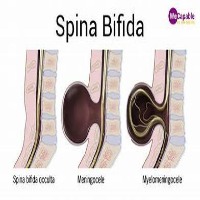

Spina Bifida